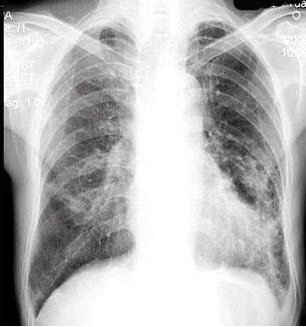

14、单项选择题 下列"脊柱转移瘤"特点,哪项正确()

男,45岁,发热、咳痰1月余,结合图像,最可能的诊断是()

A.肺脓肿

B.肺结核

C.吸入性肺炎

D.肺囊虫病

E.肺癌